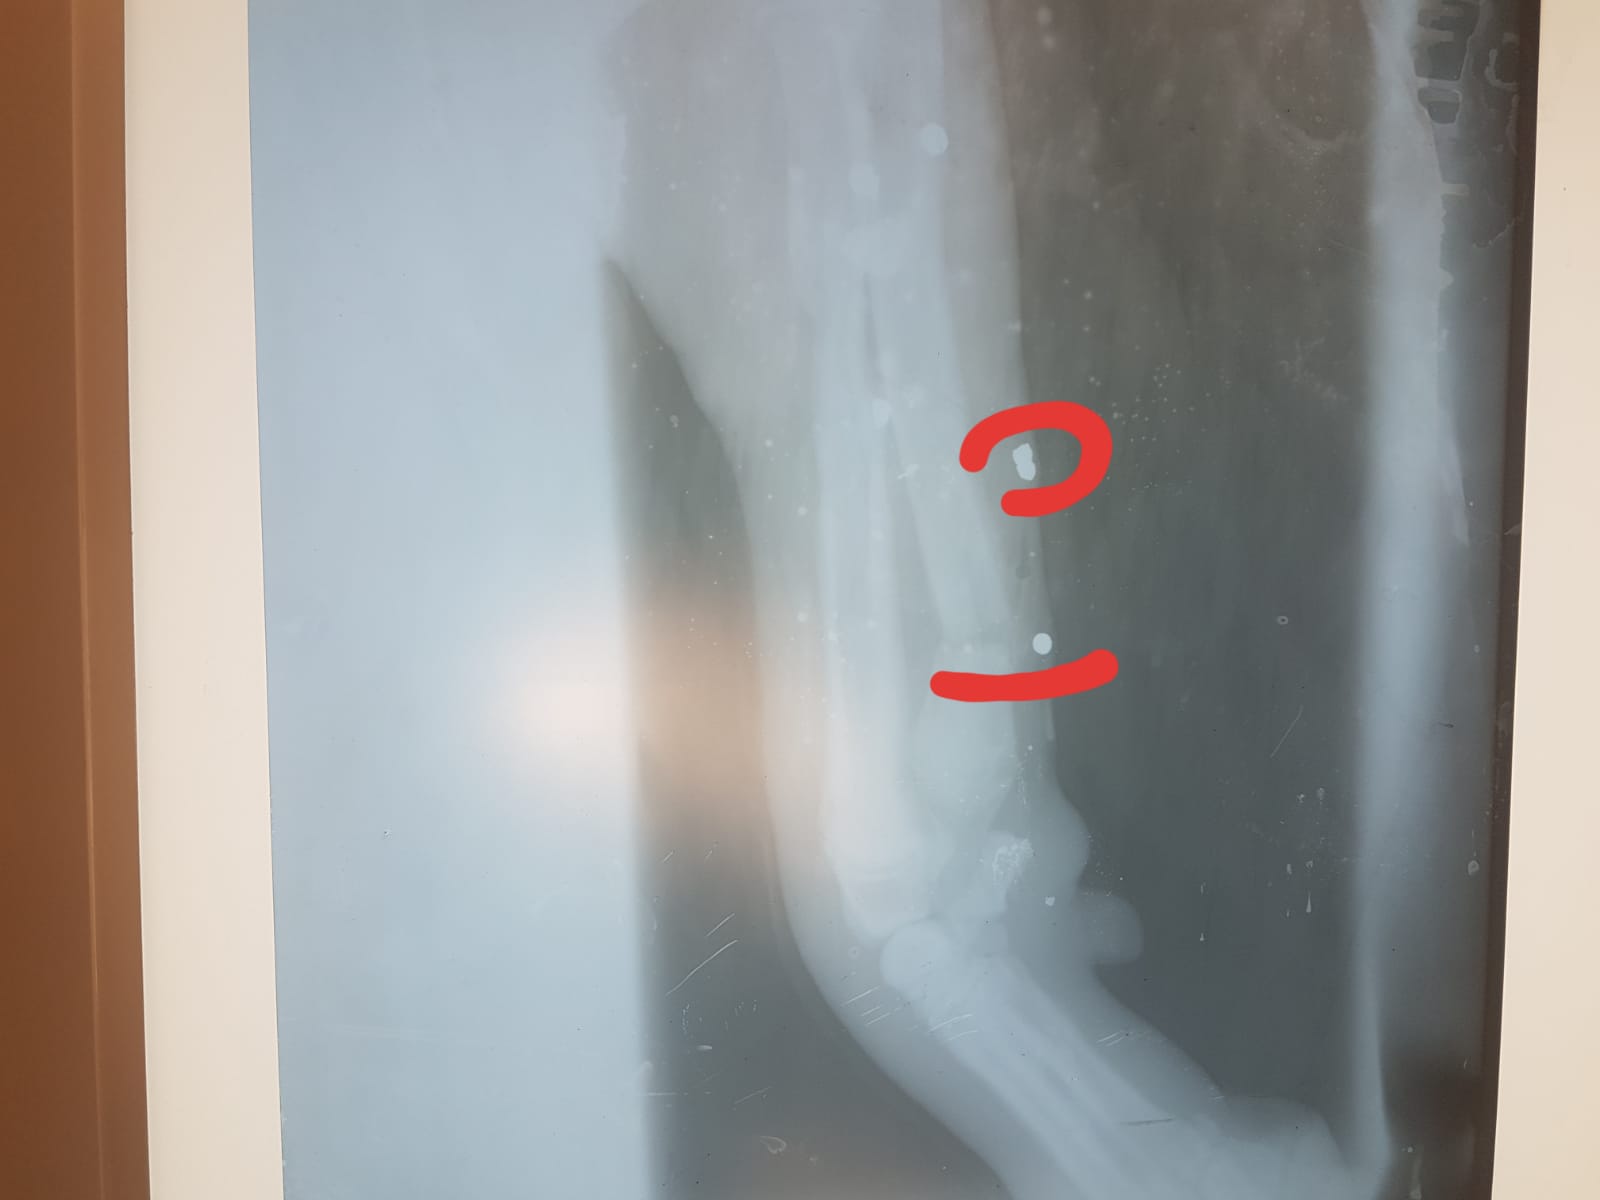

Haytap 2019 Takvim Gelirleri ile Osmaniye’ye Röntgen Cihazı Alındı

Yaralı Çoban Köpeğinin tedavisi için 75 kilometre yol kat etti